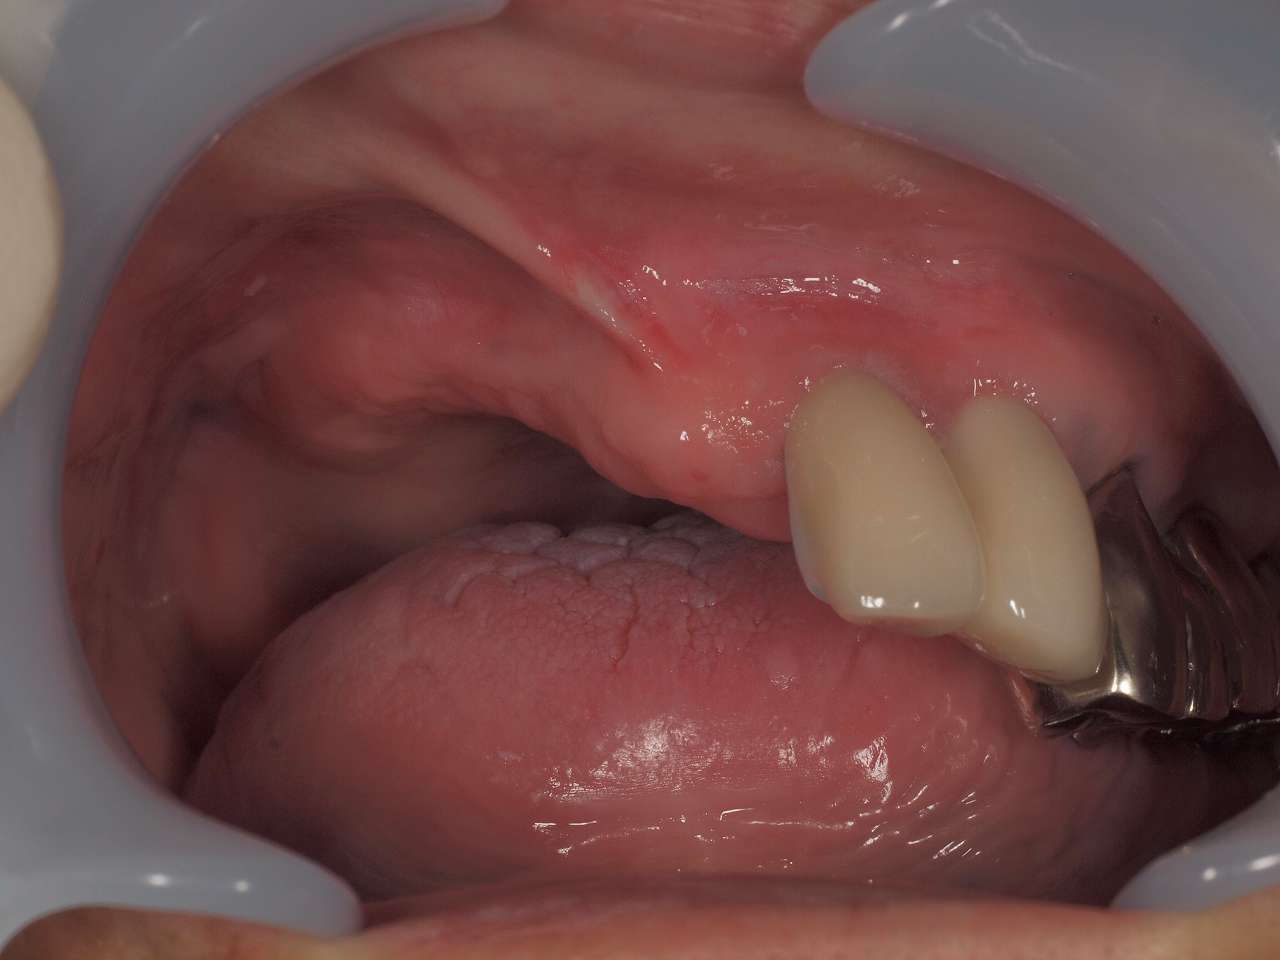

左上の2,3番部へ抜歯即時インプラント埋入を行っていきます|お知らせ |広島市安佐南区の歯科医院 左上の2,3番部へ抜歯即時インプラント埋入を行っていきます トップ お知らせ・ブログ お知らせ 左上の2,3番部へ抜歯即時インプラント埋入を行っていきます 左上の2,3番部へ抜歯即時インプラント埋入を行っていきます 術前の口腔内になります デンタルレントゲンになります インプラント埋入時になります インプラントが埋入 デンタルレントゲンになります 3か月待ちました 印象時になります カスタムのアバットメントから最終ジルコニアクラウンになります このように綺麗に入りました Web診療予約 初めての方へ 選ばれ続ける理由 院内設備について 歯が痛いしみる一般歯科 歯がぐらぐらする歯周病 健康な歯を保ちたい予防歯科 子供の虫歯予防をしたい小児歯科 銀歯をセラミックに審美歯科 白い歯を目指しませんか?ホワイトニング 矯正専門医がいるので安心矯正歯科 抜けた歯を補いたいインプラント・入れ歯 医院案内 スタッフ紹介 メリィハウス歯科クリニックオフィシャルホームページ ラベンダー歯科クリニックオフィシャルホームページ お知らせ・ブログ ホーム 診療科目 一般歯科 歯周病治療 予防治療 小児歯科 審美治療 ホワイトニング 矯正歯科 入れ歯・インプラント マウスピース矯正 初めての方へ 院長・スタッフ 設備紹介 医院案内・アクセス メニューを閉じる